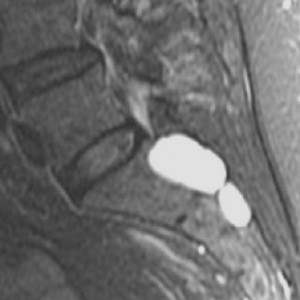

tarlov cysts